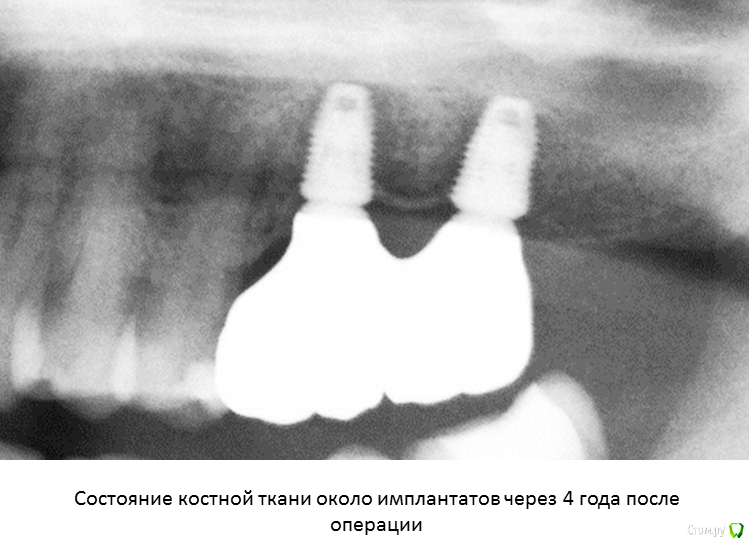

А я люблю при одномоментной имплантации цепануть верхушкой имплантата дно синуса для первичной стабильности и лунку закрыть сдт от внешнего воздействия.

Да, бикортикально, как вариант если необходима первичная стабильность